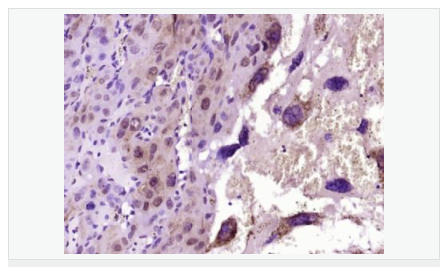

產品應用WB=1:500-2000 IHC-P=1:100-500 IHC-F=1:100-500 Flow-Cyt=1ug/Test ICC=1:100-500 IF=1:100-500 (石蠟切片需做抗原修復)

細胞定位細胞核 細胞漿 細胞膜 線粒體

產品介紹Mcl1 is an anti-apoptotic member of Bcl2 family originally isolated from the ML1 human myeloid leukemia cell line during phorbol ester-induced differentiation along the monocyte/macrophage pathway. Mcl1 localizes to the mitochondria, interacts with and antagonizes pro-apoptotic Bcl2 family members, and inhibits apoptosis by a number of cytotoxic stimuli. It is involved in programing of differentiation and concomitant maintenance of viability but not of proliferation. Isoform 1 inhibits apoptosis while isoform 2 promotes it. Expression increases early during phorbol-ester induced differentiation along the monocyte/macrophage pathway in myeloid leukemia cell lines ML1.